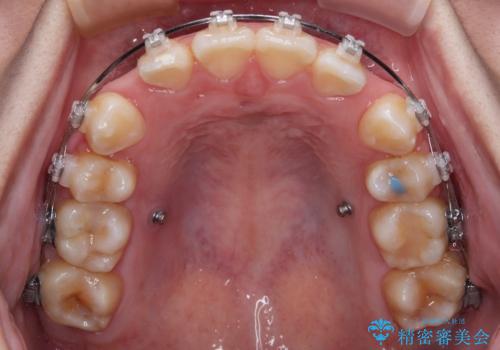

- 矯正装置

- クリアブラケット

- 転勤により東京へ移られることになり転院先を探されていた患者様です。ワイヤー矯正の途中での急な転勤なうえ、今後2~3年以内に再度転勤になる可能性もあるというご事情でした。

そのため、限られた期間内に効率よく治療を完了するために、「抜歯スペースの確実な閉鎖」「深い噛み合わせ(過蓋咬合)の改善」の2点を主軸とした治療計画を立てました。

結果的に1年半で、再度転勤になる前に治療を終えることができました。